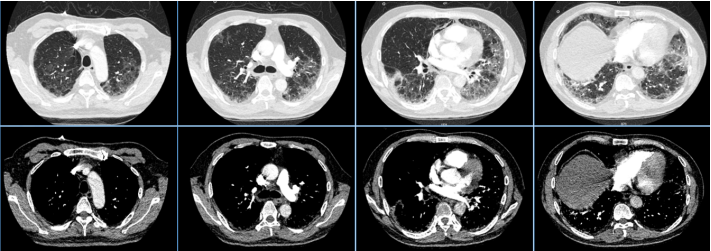

患者,男性,39岁,双肺弥漫性间质性炎(图14)PaO53 mmHg、Ⅰ型呼吸衰竭,高流量吸氧及无创呼吸机辅助通气无明显改善,收住RICU,行冷冻肺活检提示:肺泡蛋白沉积症(图15)

图片

图14  患者胸部CT

MDT意见:难以纠正的呼吸衰竭;肺功能差;灌洗过程中可能出现急性肺水肿;难以耐受长时间全身麻醉。予清醒VV-ECMO+大容量肺泡灌洗。患者氧合得以纠正,病情好转(图16)

图16  患者肺泡灌洗前后比较